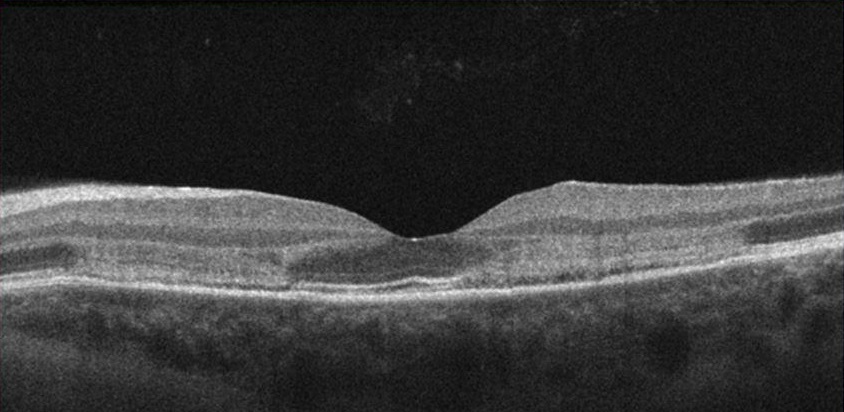

AMN in 22 year old female that presented with bilateral paracentral scotomas and blurry vision. Presenting BCVA was 20/20 OD and 20/25 OS.

Right eye: